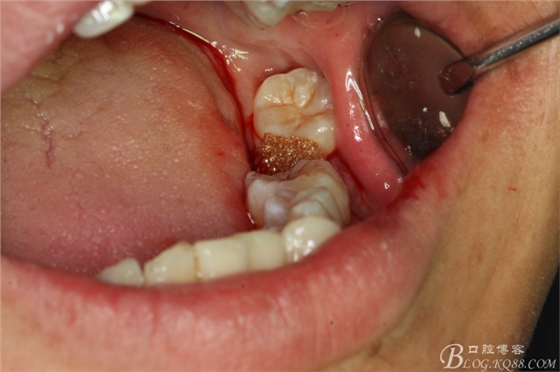

圖8.先橫斷47牙冠,盡量從牙頸部橫斷

圖9.潛掘法橫斷牙冠

圖10.橫斷牙冠的影像

圖11.牙挺分開(kāi)47牙冠

圖12.挺出47頰側(cè)牙冠